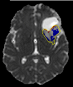

Chemiotherapic Follow-up of Brain Gliomas

Brain

gliomas invade surrounding tissues

along white matter fibers, spreading beyond the pathological area

highlighted by conventional MRI (Magnetic Resonance Imaging). The

response to chemotherapy treatment

is currently assessed on the basis of the variation in tumor volume,

often carried out visually. The system we have developed, in

collaboration with the IRCCS San Raffaele Hospital and Università

Vita-Salute San Raffaele, Milan (Neuroradiology Unit), performs a

point-by-point assessment based on diffusion tensor maps.